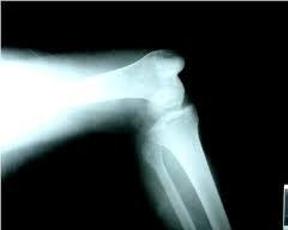

膝关节骨性结构虽不稳定,但关节周围和前节内有较坚强的韧带和肌肉保护,故膝关节脱位较为少见。偶有脱位也是在强大的直接暴力撞击胫骨上端或间接暴力使膝关节受旋转或过伸性损伤,致胫骨上端向后、向前两侧脱位。完全脱位时,不仅关节囊破裂,十字韧带、内外侧副韧带、半月板以及周围肌肉的撕裂;甚至合并胫骨棘、胫骨结节撕脱性骨折和股骨髁骨折。内侧脱位严重者可发生腓总神经牵拉性损伤。严重后脱位者,可致腘动、静脉破裂、栓塞、压迫,引起肢体坏死和缺血性挛缩。